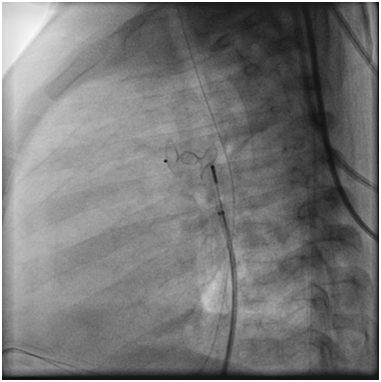

Angiography at the beginning of the cath showed that the PDA had completely disappeared (Figure 3).

Figure 3 Angiogram in the Aorta showed that the PDA disappeared.